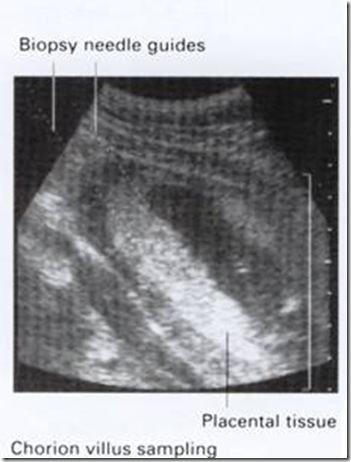

clip_image008

Pada trimester I, chorionic villi sampling dilakukan dengan panduan ultrasonografi , pengambilan jaringan dapat dilakukan transvaginal atau transabdominal. Prosedur ini dilakukan sekitar kehamilan 11 minggu. Dan abortus pasca tindakan CVS sekitar 4%